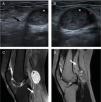

Ultrasound (A, B) and MRI (C, D) images of the knee depicting a well-defined solid mass (*) localized in the popliteal region, originating from the tibial nerve (arrows), with a heterogeneous structure with low intensity MRI-signal on T1 sequences and high intensity on DP SPAIR (C) and T2 sequences (D).

A 36-year-old healthy woman (Fig. 1) presented with a five-year history of a slowly enlarging mass in the popliteal region, with no previous history of trauma. A mobile and solid mass was palpable at the popliteal region evocative of a Baker's cyst, although the Foucher's sign was not present on examination. The patient was referred for ultrasound-guided aspiration and corticosteroid infiltration. However, ultrasound (US) documented a 29.9×25.5mm heterogeneous solid mass in the popliteal region, originating from the tibial nerve. Magnetic resonance imaging (MRI) showed a homogeneous low intensity in T1-weighted images and heterogeneous high intensity in T2-weighted images, suggestive of a tibial nerve schwannoma.